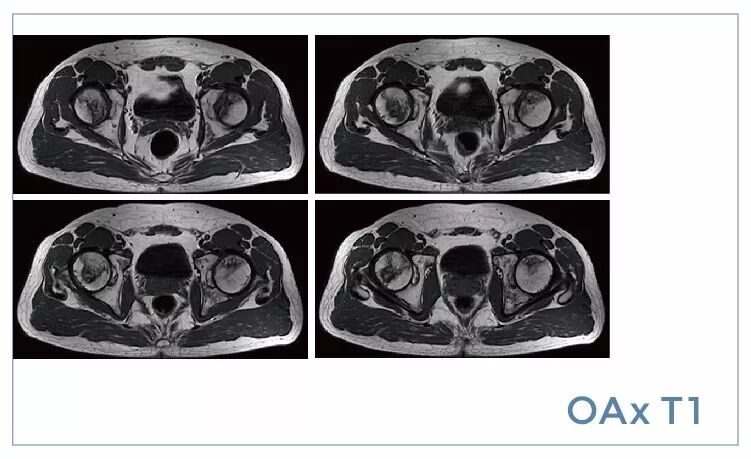

【朗润影像档案】20190719磁共振影像病例结果讨论